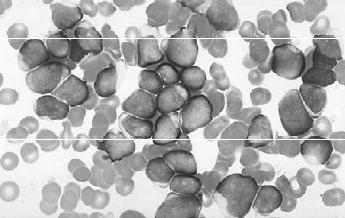

1976年法、英、美三国制订了FAB分型诊断标准,1985年以后又有多次小的修正。目前FAB的分型诊断标准已为世界各国广泛应用,虽然近年世界卫生组织(WHO)提出了新的分型诊断标准,目前已逐渐被广泛采用(见图3—1、图3—2、图3—3),现介绍FAB分型诊断标准要点如下。

图3—1 ALL—L骨髓象

图3—2 ALL—L骨髓象

图3—3 ALL—L骨髓象

1.ALL(表3—1